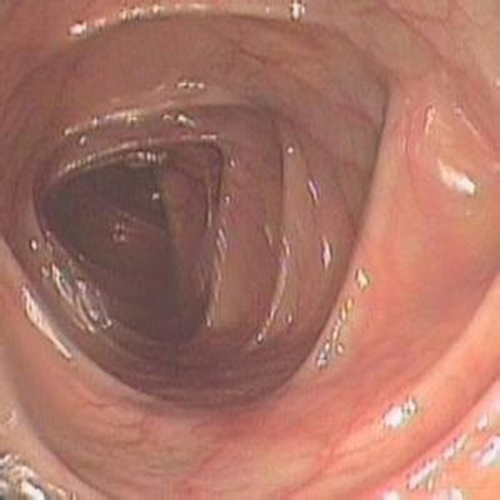

早期慢性結腸炎的

纖維結腸鏡檢查